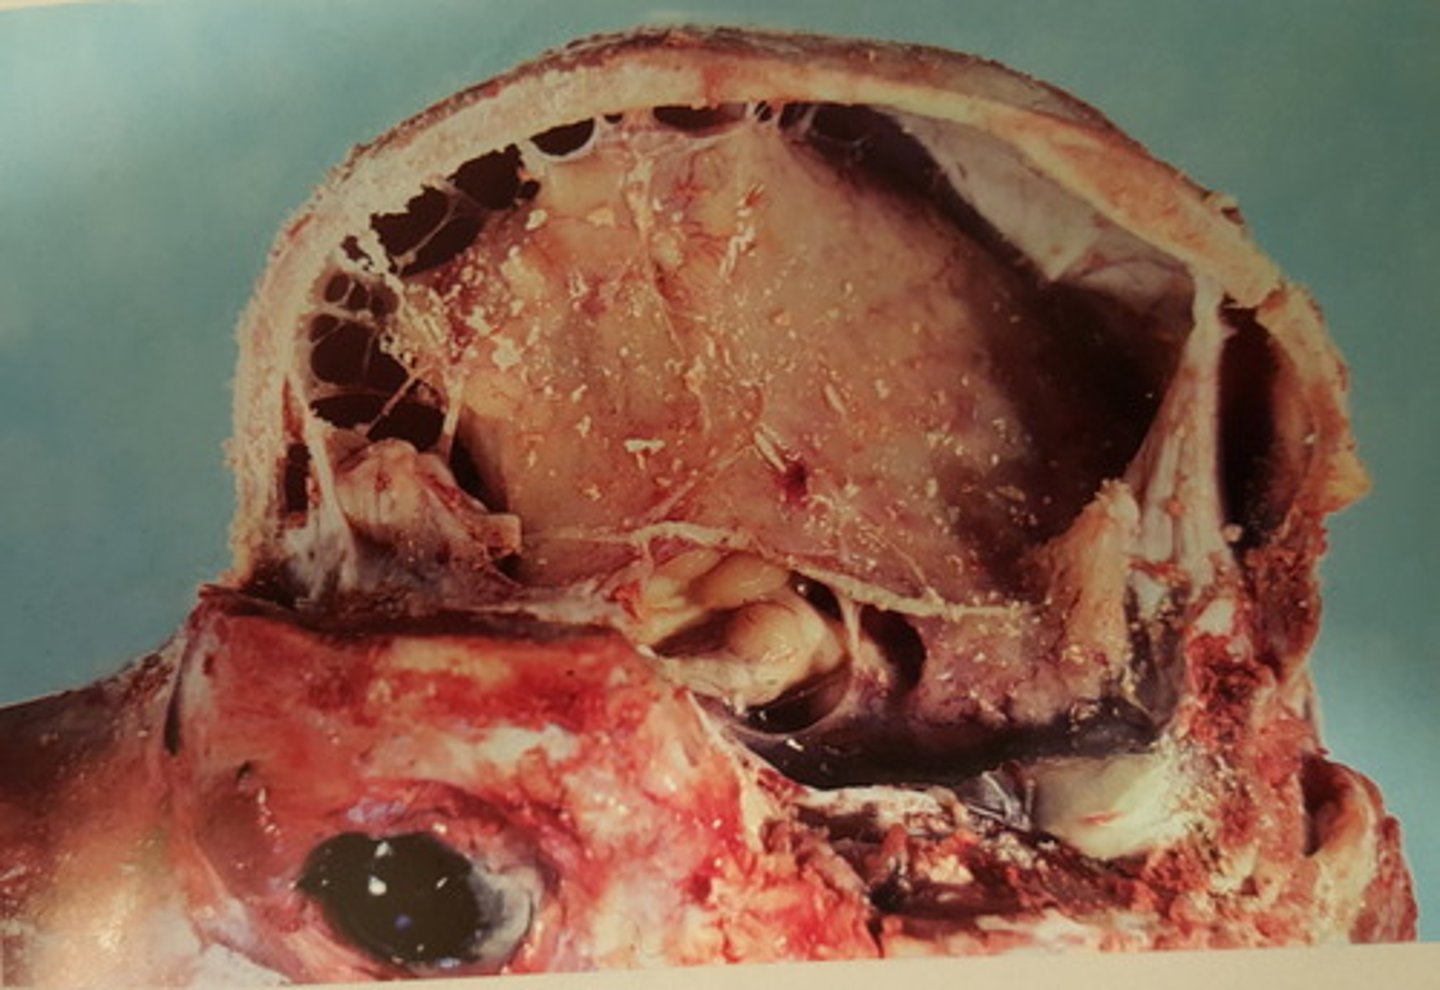

Benign hypofyseneoplasi med hæmorrhagi

Hovede fra hest, hvad er den patoanatomiske diagnose? Se pilen

benign hypofyse neoplasi med hæmorrhagi

Gennemskåret hestehoved. Patoanatomisk diagnose?